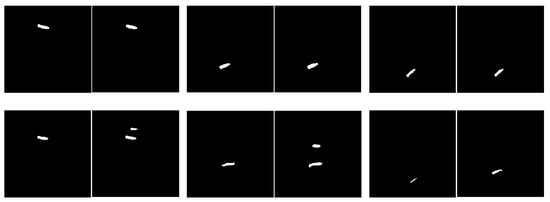

Next, experiments are conducted to evaluate the accuracy of various different methods. The approach proposed in this study needs to be compared with five other different models to evaluate the performance of different methods, including U-Net [12], CNN-based [13], Attention U-Net [14], Multi-ResUNet [16], and the two-stage Multi-ResUNet model [30]. A comparison between the proposed method and the experimental data of the aforementioned five models is shown in Table 4. The steps of the proposed method are to perform the sub-image cropping method and the sub-image disc segmentation method on the two lower target discs (L4/L5 and L5/S1), and to perform the data-augmented segmentation method on the upper disc (L1/L2). The comparison results show that with a confidence interval of 95%, the accuracy of the proposed approach reaches 97.7 ± 1.6%, the mean IoU is 77.0 ± 0.4%, and the SSIM is 0.6916 ± 0.0115, surpassing the performance of the other five models. Figure 8 shows the results of the proposed approach. The upper row shows the correct results, and the lower row shows the error results. In each pair of images, the left image is the standard mask, and the right one is the prediction result. The three target intervertebral discs (L1/L2, L4/L5, and L5/S1) in the top row of Figure 8 are accurately segmented. In the bottom row of Figure 8, the case on the left is an error in the segmentation of the two lower target intervertebral discs (L4/L5 and L5/S1), and the case on the right is an error in the segmentation of the upper intervertebral disc (L1/L2).

Figure 8. Sampling results of the proposed approach. The upper row shows the correct results, and the lower row shows the error results. The left side of each pair of images is the standard mask, and the right side is the predicted result.